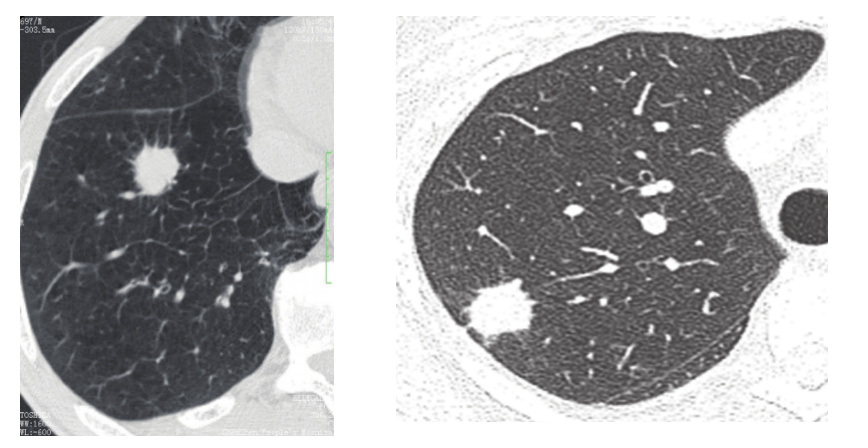

周围型肺癌征象之分叶征,毛刺征,棘状突起

棘状突起:肿瘤细胞局部浸润,是介于分叶和毛刺之间粗钝的杵状结构2.

毛刺形成机制:肿瘤组织中含有向内收缩的纤维组织,致使肿瘤边缘出现较